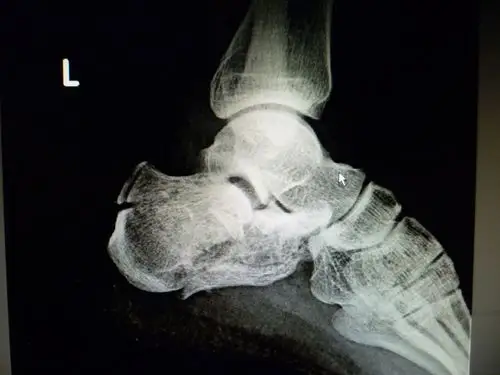

左脚跟骨,骨折需要手术吗,懂行的帮我看哈

左侧跟骨骨折

左跟骨骨折,求手术方案?

左跟骨骨折

吴海林,男,29岁,左跟骨骨折

左脚跟粉碎性骨折